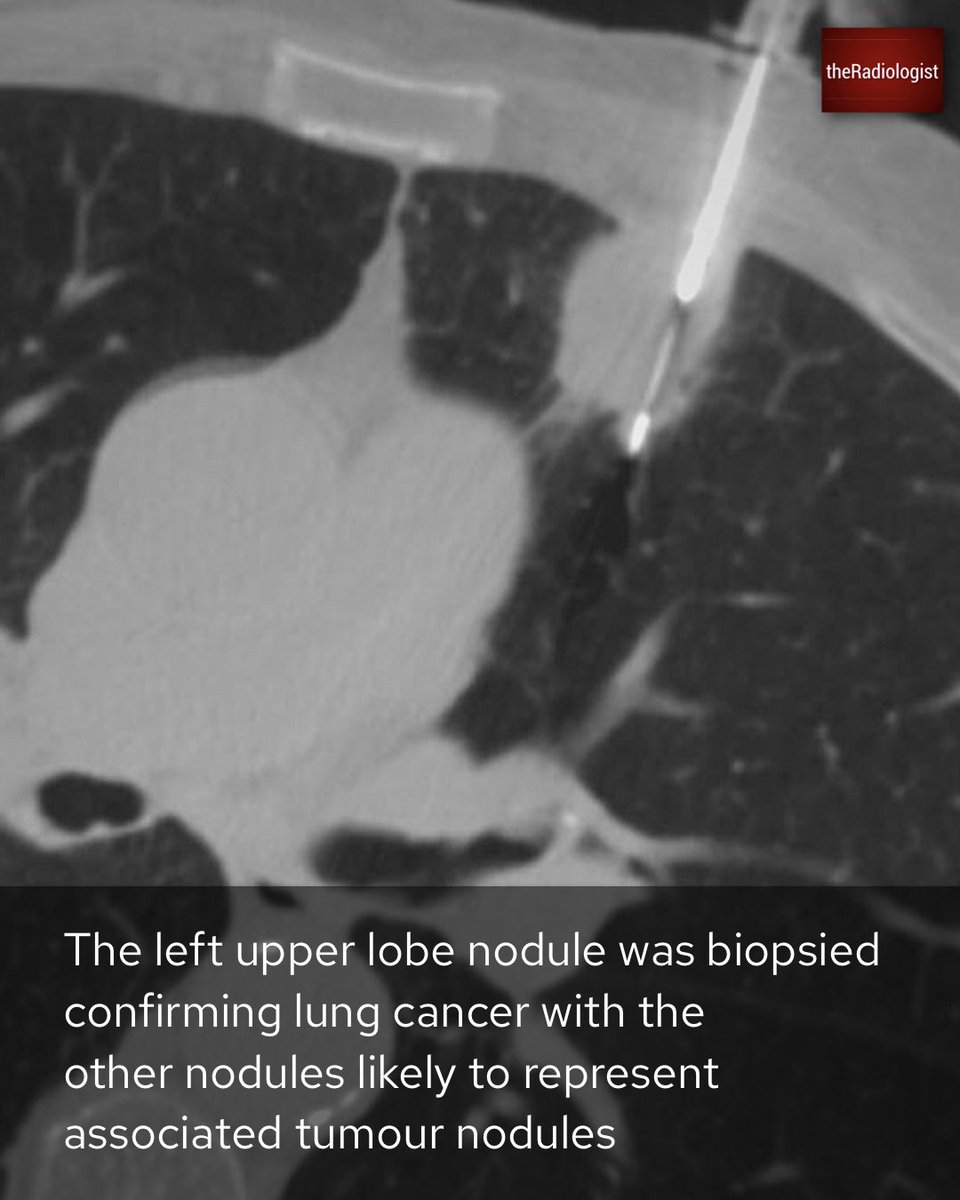

Explanation 3/3